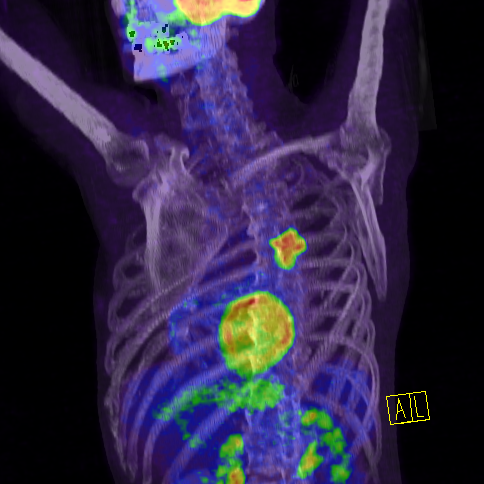

PET/CT înseamnă aplicarea în acelaşi timp a două metode de examinare. Cu ajutorul CT pot fi identificate modificările patologice, anatomice şi structurale ale organelor, dar, în acelaşi timp, deficienţa acestuia este că nu oferă informaţii despre comportamentul biologic al modificărilor. Cu ajutorul tomografiei cu emisie de pozitroni (PET), devine vizibil metabolismul ţesuturilor examinate. În cursul examinării PET, cel mai des este administrată molecula glucoză (FDG), marcată cu izotopul (18F). Cu ajutorul FDG putem obţine informaţii despre consumul de glucoză al ţesuturilor. Cele mai multe tumori maligne se dezvoltă foarte repede, de aceea consumul de glucoză este mai intens. PET identifică tumorile folosind aceste caracteristici.

Imagine PET/CT a unei tumori pulmonare centrale pe partea stângă. Se observă că tumoarea malignă acumulează FGD, dar încă nu a dat metastaze în nodulii limfatici locali sau metastaze îndepărtate.